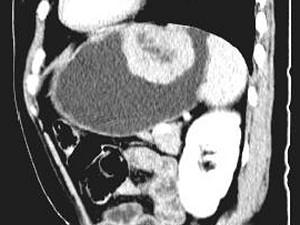

问题 女,51岁,上腹部隐痛不适,CT检查如图,可能的诊断是 ( )

选项 A、胃溃疡 B、胃间质瘤 C、胃息肉 D、胃腺瘤 E、胃癌

答案 B